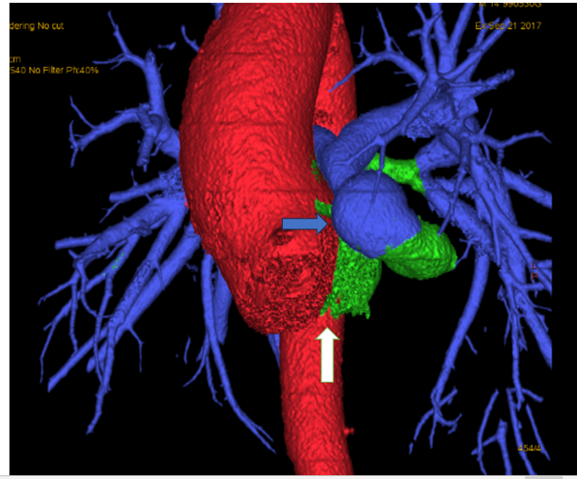

He underwent MRI cardiac and that suggested the presence of a common arterial trunk originating from the left ventricle, associated with a large subaortic ventricular septal defect (VSD). (Figure 2) His CT cardiac showed that the common trunk has three cusps, with the left and posterior-facing cusps being enlarged and giving rise to the main pulmonary artery. The main pulmonary artery was notably elongated and tortuous, forming a near semicircular arc before assuming its typical anatomical position to the left of the ascending aorta. (Figure 3)

Figure 3: Common trunk (White arrow) which continues as ascending aorta, main pulmonary artery (Blue arrow) which is tortuous and elongated arising from the posterior aspect.